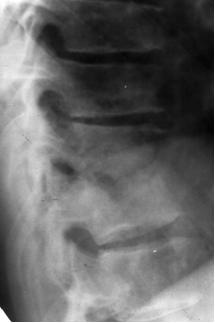

Ламинэктомия с транспедикулярной фиксацией. 1-тело позвонка; 2-дужка позвонка; 3-титановый винт; 4-ламинэктомия.

- Задняя ламинэктомия (удаление дужки позвонка) может быть достаточной для экстренной декомпрессии нервных структур. Ламинэктомия обычно дополняется стабилизацией позвоночника, так как может развиться нестабильность. То есть выполняется транспедикулярная фиксация (ТПФ) – в тела позвонков через корни дужек (ножки) вводятся титановые винты, которые затем скрепляются продольными балками и иногда поперечной. Если выявлен гной, то ТПФ выполнять опасно, так как металлоконструкция все-таки инородное тело и может привести к хронизации гнойного процесса. В таком случае ТПФ обычно выполняется вторым этапом только после излечения эпидурального абсцесса. При отсутствии признаков остеомиелита позвоночника после проведения простой ламинэктомии или гемиламинэктомии на одном уровне и антибактериальной терапии антибиотиками нестабильность обычно не развивается. При выявлении гноя операция заканчивается установкой дренажной промывной приточно-отточной системы. Если выявлена только грануляционная ткань, то установка промывной системы не требуется.